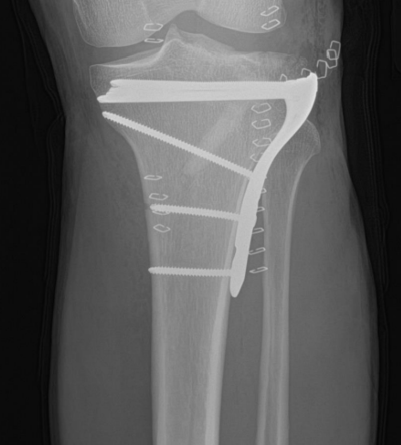

<p>What is wrong with this patient?</p>

What is wrong with this patient?

Nothing, this is a pediatric radiograph. The lines show epiphyseal plates